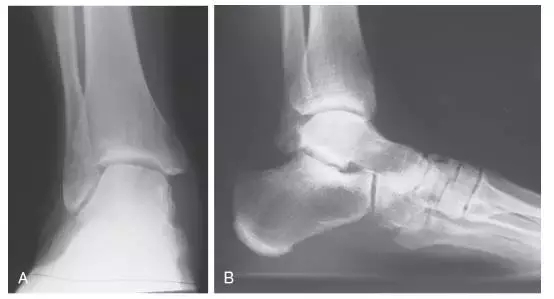

上述旋转由踝关节通过距下关节传导至跟骨和足部。关节炎,创伤,手术,或先天性异常等可导致距下关节运动功能丧失。而上述旋转功能丧失会导致该固定关节临近的关节如踝关节、跗横关节等应力增加,进而引发慢性疼痛。上述应力的增加可能会引起进一步损伤而导致球窝状踝关节(ball-and-socket ankle joint)的形成(图2)。此外在一个距下关节融合的患者还可能会出现距舟关节的损伤(图3)。

图2 成人球窝状踝关节的形成。A 由于先天性畸形导致的距下关节活动丧失,踝关节代偿了距下关节的横向旋转。B 该患者先天性距舟关节融合,导致距下关节运动的丧失,使踝关节代偿横向旋转,最终导致球窝关节的形成。